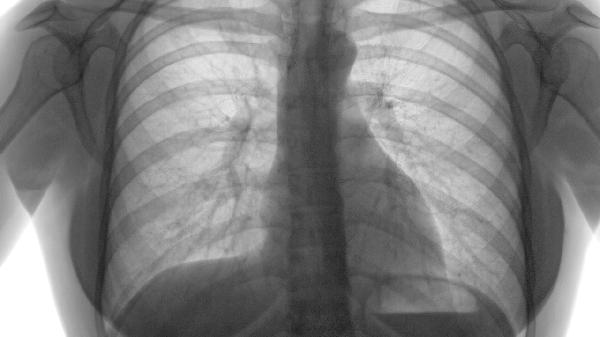

肺氣腫

肺氣腫要檢查血氣分析嗎

肺氣腫嚴重時(shí)需要檢查血氣分析。對于肺氣腫的診斷主要是通過(guò)做肺功能檢查,能夠了解目前氣道受阻的程度以及氣道的通暢程度,從而確診肺氣腫的嚴重程度。但如果肺氣腫病情比較嚴重時(shí),需要做血氣分析,通過(guò)血氣分析的數據,能夠了解目前肺氣腫的治療情況。另外,對于肺氣腫一般是積極藥物治療,并且可配合氧療、營(yíng)養支持治療等。